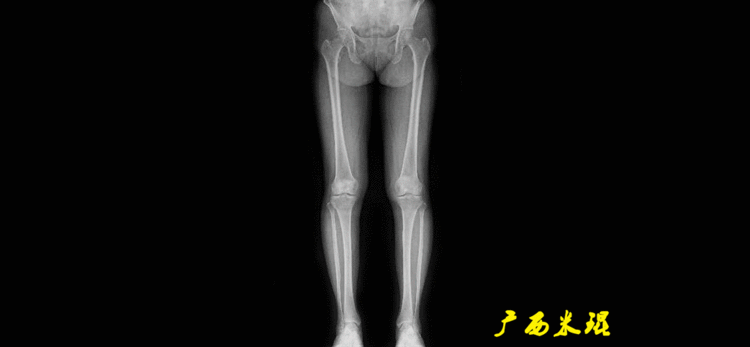

下肢力线及相关角度测量的前提是必须拍摄标准的站立位也就是负重位的下肢全长片。目前这样的照片都是放射科的技师在电脑上拼接出来的,大部分医院的DR都能够做到这一点。

患者直立于摄影架上,后背贴近摄影架,双手自然下垂,膝关节尽量伸直,足部与双肩同宽,要求投照时双髌骨朝正前方,通常患者双足尖应平行向前即可。

提醒一下大家,拍摄过程中应避免下肢的外旋和内旋。如果有一侧肢体短缩时,投照应当用脚垫垫高短缩肢体,使骨盆保持水平,这样下肢短缩测量才精确。如果有肢体旋转畸形时,还是以髌骨朝前为标准,虽然此时双足可能不能保持平行。

二、下肢全长片的基本要求

无论如何,拍摄出来的下肢全长片必须包含髋关节中心、膝关节中心及踝关节中心,否则对临床是无用的。有了一张下肢的全长照片,我们需要确定下肢关节的中心点,通过中心点画出下肢的各种轴线,然后利用轴线与关节线的相交得出各种所需要的角度。